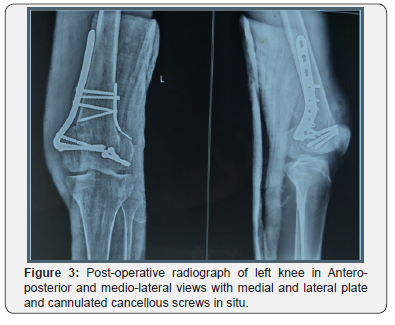

We used proximal tibial plate on medial side and precontoured distal radius plate on lateral side along with 4.5mm Cannulated cancellous screws to fix the fracture (Figure 3). Physiotherapy of the muscles was carried out. After the healing of skin lesions, we had immobilized knees by the cruro-pedious resins for 04-week. At the end of this period, we proceed with the removal of the resin. The fact of removing is able to thaw the resumption of physical therapy for a period of 6 weeks. Onefollows up radiograph was undertaken externally every month until consolidation. At final follow- up of 3-month functional assessment of the patient score was excellent with 90 degrees flexion, an absence of laxity and an absence of pain. Patient was lost to follow up after 3 months.